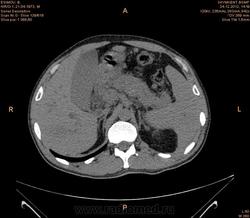

Предварительно образование головки ПЖ, и в печени. Что с ферментами?

на операций рак головки подж.железы с метастазир. печень.

инфильтрация тут нисходящей 12 перст кишки , расширенного холедох,расширенный вирсунгов проток ,нижная граница очень близко прилежит к нижней полой вене с правой почечной веной ,но четко визуализирутся передний листок фасции Героты(нельзя исключить ее инфильтрацию), инфильтрация конгломератом увеличенных лимфатических узлов ворот печени портальной вены с варикозным расширением вен, на вышележащий срезах четко определяются верхняя брыжеечная вена и артерия ,не хватает срезов для полной визуализации(помогли бы мпр),инфильтрирована восходящая ободочная кишка,конгломерат лимфат узлов за головкой поджелудочной железы в виде гиподенсивного участка вытянутой формы , ,мтс в печень,парааортальные